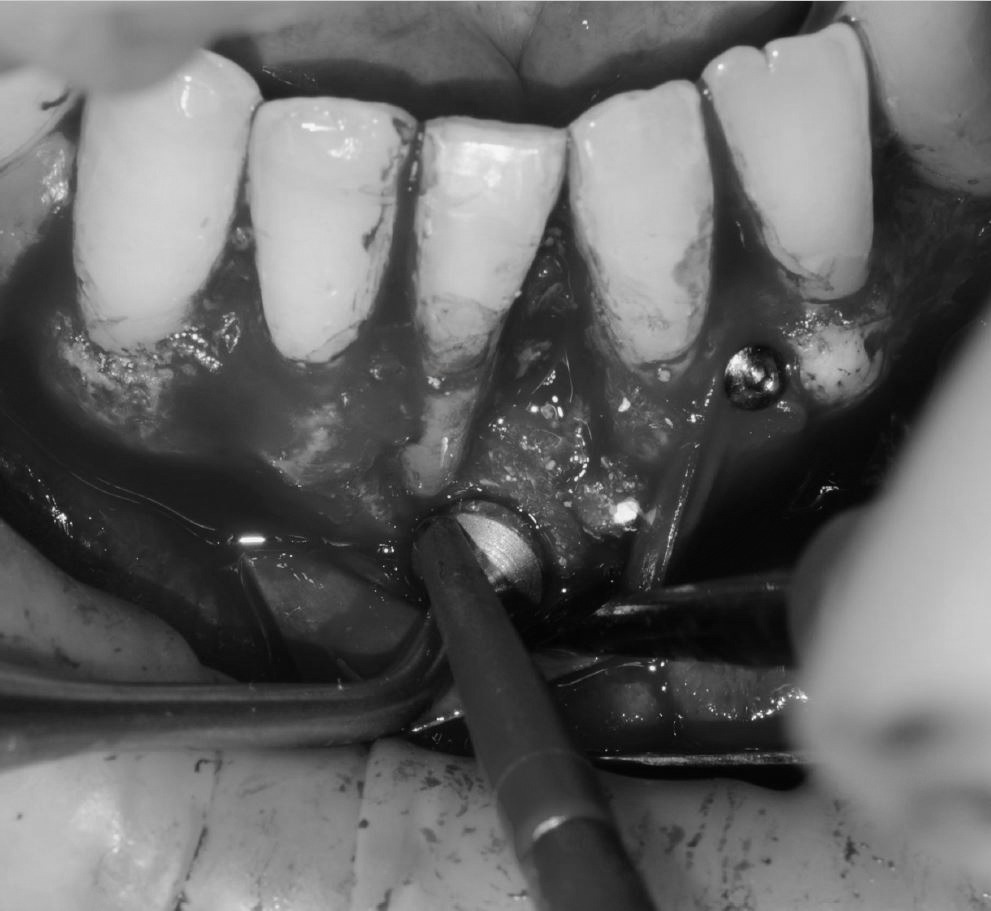

Objetivos periodontales: Regeneración osea guiada con bioss collagen y emdogain.

- Eliminar tejido necrótico. Regeneración periodontal cemento, ligamento y hueso

- Mejora de la estabilidad y soporte óseo

- Estabilidad periodontal y reducción de la movilidad

R.A.R. Profundo suave intraquirúrgico

Aplicación protocolo emdogain

Regeneración ósea guiada con membrana de colageno creos de Nobel Biocare y relleno óseo mediante BIOSS Collagene de INIBSA, con elementos de fijación a la membrana para R.O.G.

Fotografías del proceso: